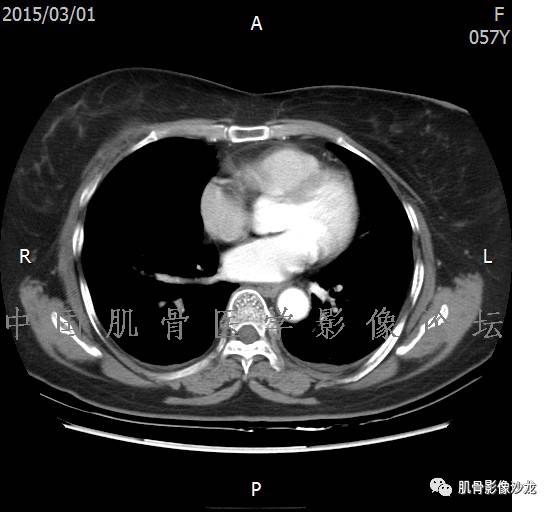

患者于2月前无明显诱因下出现腰骶部疼痛,夜间为重,逐渐加重伴左下肢麻木、疼痛,并有行走活动受限,在我院就诊,摄腰椎及骶髂部CT提示:腰椎骨质退变,腰3-4、4-5椎间盘膨出,骶髂关节炎。自用非甾体抗炎药无好转,再次来院就诊,门诊拟“骶髂关节炎”收住我科。病程无间歇性跛行,大小便正常。

专科检查:神清,脊柱无侧弯后凸畸形,椎体各节段无压、叩痛,双侧棘突旁无压痛,双侧骶髂关节压痛明显,左下肢放射痛,浅感觉较健侧减退,腰椎前屈后伸活动受限,膝、跟腱反射正常。

辅助检查:腰椎及骶髂部CT提示:腰椎骨质退变,腰3-4、4-5椎间盘膨出,骶髂关节炎。

雪舞 :第二例,位于骶骨,有骨质破坏并有软组织肿块,软组织肿块边界清

雪舞 :第二例挺难的,骨质破坏是溶骨性的,局部皮质中断,软组织肿块外缘光滑

1、软骨肉瘤可以有膨胀性骨质破坏(病例3,4),可以有溶骨性骨质破坏(病例2),局部皮质因为破坏变薄,中断 ;

2、软骨基质T2WI高信号,软骨小叶分叶状,也就会出现高老师提到的骨内膜扇贝形压迹。一般认为骨内膜扇贝形压迹超过骨皮质厚度的2/3是软骨肉瘤在长管状骨的特征性表现。如上图。3、软组织肿块或肿胀;

4、 钙化,环形,弓形,边缘模糊 ;

5、增强后进行性延迟,不均匀分割状强化, 会强化的纤维间隔,软骨小叶不会强化,关于老师们说到的钙化,软骨肉瘤不一定会有钙化 。